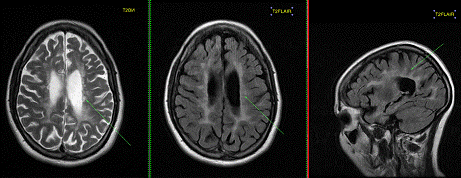

МРТ центральной нервной системы

МРТ сердца МРТ желудка и кишечника